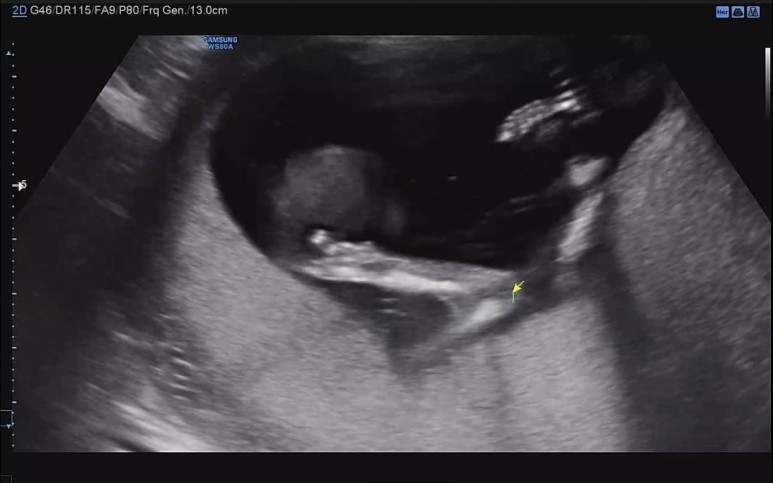

16주차 산부인과 정기검진

또다시 기다림의 4주가 지나고. 드디어 정기검진일.

16주가 되면 성별을 대략 알수 있다고 해서 어찌나 두근두근 콩닥콩닥 하던지.

꿀잠이 오늘은 똑바로 앉아있기.

4주가 지나니 이제 척추뼈가 하나하나 다 보이고 머리도 훌쩍 커진게 눈에 보인다.

일단 심장소리. 쿠궁쿠궁.

꿀잠이 오늘의 바이탈 144bpm!

쭉 뻗고 앉아있는 귀여운 ㅋㅋ 다리 ㅋㅋ

요기는 팔꿈치.

손을 머리쪽으로 올리고 있다.

이제 초음파 영상 구분하는 고수가 되어서 어디가 어딘지 척척.

콧대도 확인하고.

벌써 머리통이랑 콧날이 예쁜것 같아 내새꾸.

초음파 선생님이 엉덩이 사이를 열심히 들여다 보셨지만, 탯줄이 교묘하게 가리고 있어서 도저히 성별을 가늠할 수 없다고 하셨다. 그런데 내 느낌엔 슬쩍 슬쩍 지나가는 화면에 다리 사이에 아무것도 보이지 않는게 자꾸 포착되어서 딸인것 같은 느낌적인 느낌을 느꼈다..!